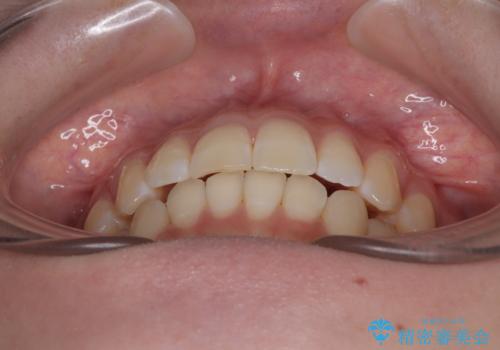

- 上下前歯の重なりを気にして来院された患者様です。

安価なインビザラインパッケージを用いての治療を希望されており、デコボコの程度が中等度であったため、インビザライン・モデレートを用いて矯正治療を行うこととしました。